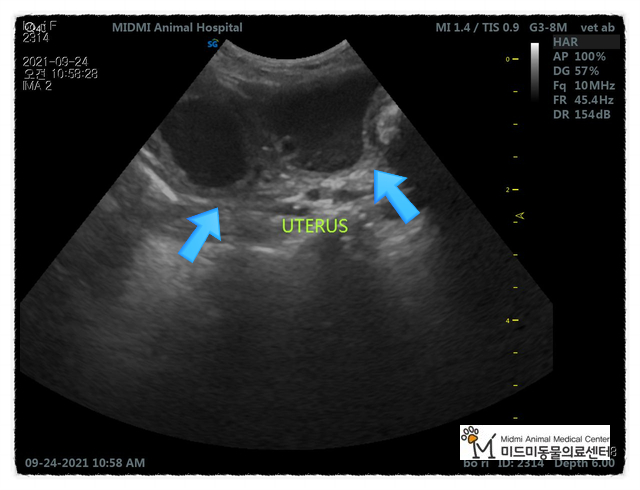

저희 병원에서 방사선, 총음파 검사 후 개의 자궁 축농증으로 진단되었습니다.

수술 전 혈액검사, 초음파검사, 방사선촬영을 통해 수술 전 컨디션을 체크한 후 수술을 결정했습니다.